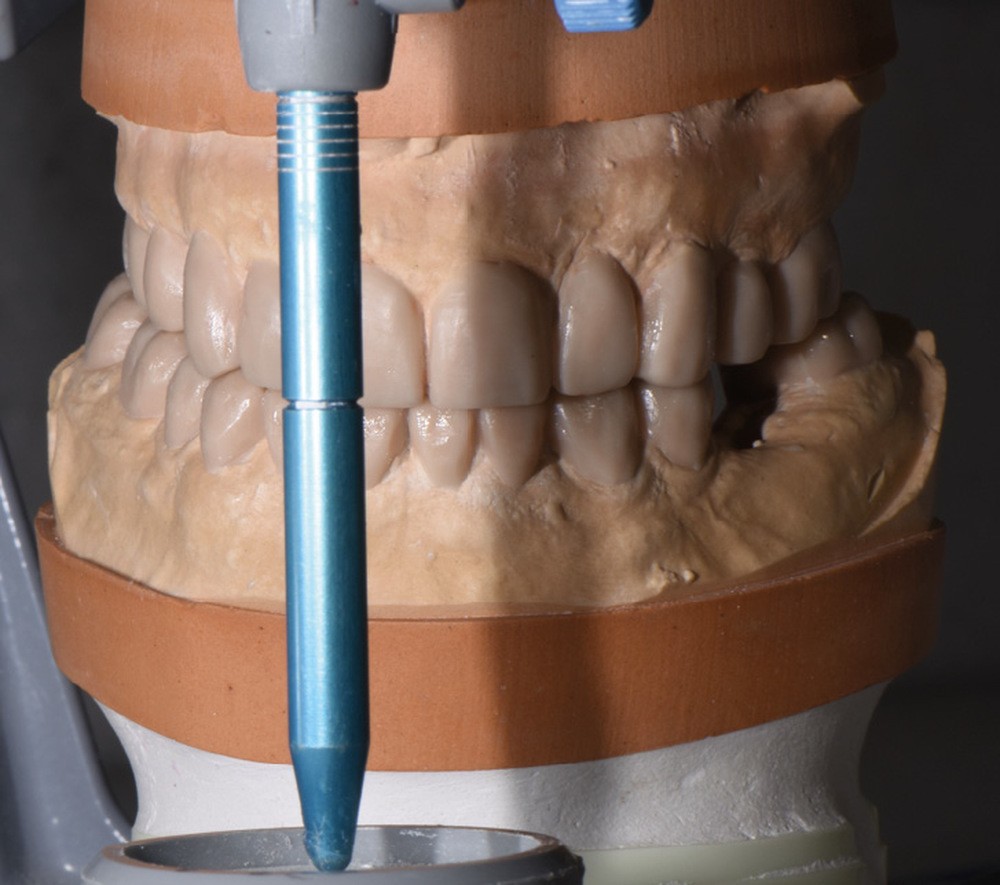

Au vu du contexte para-fonctionnel et de l’étendue de la perte tissulaire, des coiffes périphériques minimalement invasives ont été choisies afin de restaurer l’esthétique et la fonction. Actuellement, aucun consensus n’est fait sur le choix du matériau d’infrastructure à privilégier. Les matériaux hybrides usinables présentent des propriétés mécaniques, physiques et biologiques intéressantes en contexte d’usure sévère (e.g., module d’élasticité, résistance à la propagation de fêlures, facilité de réintervention). Une réhabilitation globale avec remontée de dimension verticale d’occlusion (DVO) par l’intermédiaire de coiffes composites renforcés en nano-céramiques est décrite.